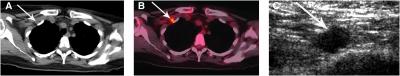

Reston, Va.—In the largest study to date to evaluate fluorodeoxyglucose positron emission tomography combined with computed tomography (FDG-PET/CT) in the initial staging of inflammatory breast cancer (IBC), researchers were able to identify the precise location and extent of metastasis (spread of disease), offering the potential for a better prognosis for patients with this rare, but aggressive form of breast cancer.

Each patient underwent a whole-body FDG-PET/CT exam. The scans showed that nearly half of the patients (49 percent) had distant metastasis, and 27 percent had disease in multiple sites. Neither finding had been previously detected by conventional imaging. These results were confirmed by biopsy and supplementary imaging.

"Breast cancer is a systemic disease, not just a local one. Most imaging modalities are localized and will therefore miss the spread of disease that is frequently present by the time IBC is diagnosed," Macapinlac said. "The use of a whole-body modality such as PET/CT with its higher sensitivity, however, allows us to pinpoint metastasis in other parts of the body; for example, behind the clavicle—which can not be detected in a physical exam—or in the abdominal organs or pelvic lymph nodes."

PET provides information about how the body is functioning at the cellular level, while CT provides an anatomical rendering of the inside of the body. In an FDG-PET/CT scan, the CT first produces detailed images of the inner anatomy of the body. The patient is then injected with a small amount of a radioactive drug, which is F-18-labeled glucose, and PET is performed. Because fast-growing cancer cells feed on sugars such as glucose, PET/CT delineates areas where the glucose accumulates in the body, identifying the location of cancer cells.